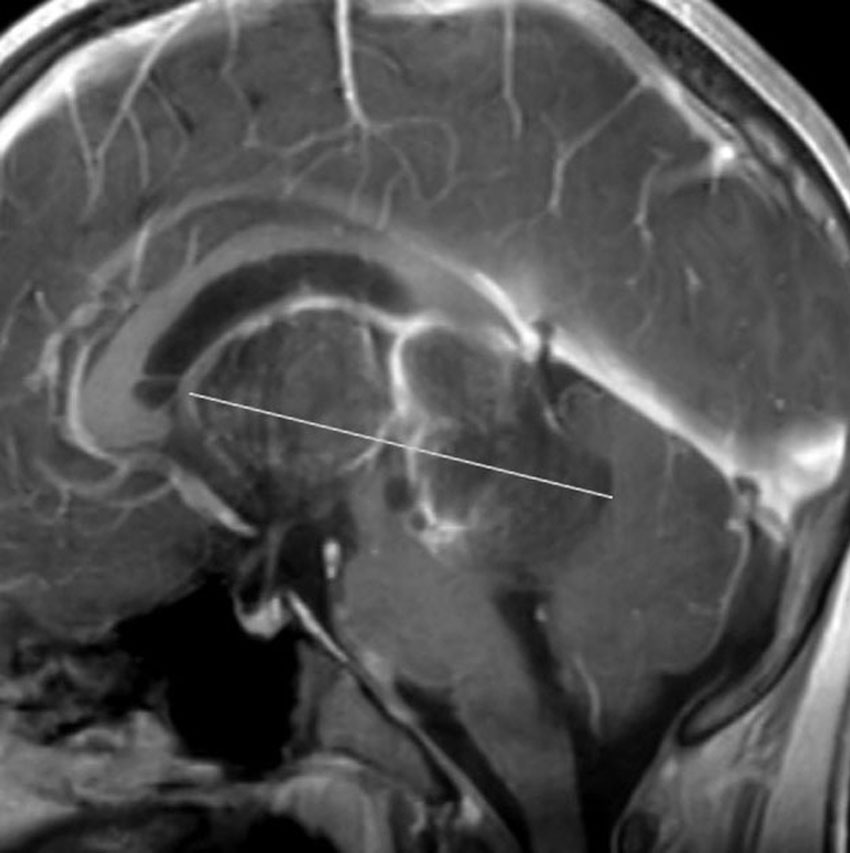

teratomaのparadoxical response

neurohypophyseal mixed germ cell tumorの若年成人男子例です。発症時のMRIでは大部分が増強されますが,腫瘍の右前方に脂肪組織を示す小さな信号域を認めます(上段左の単純MRI,上段右の増強MRI)。経蝶形骨洞生検術でmature teratomaとgerminomaの所見が得られました。ICE化学療法により増強される部分の腫瘍は消失しましたが,逆に下段左の単純MRIと下段中央のCTで認められる脂肪組織を含む部分が顕著に増大しました。この腫瘍は後に亜全摘出しました(下段右)が,病理所見は類皮腫でした。teratomaにおいてはこのような奇異な治療反応性 paradoxical response がみられることがあります。